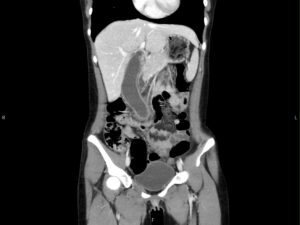

Hydropic Gallbladder. CT, Coronal, Unannotatd. JETem 2025

Hydropic Gallbladder. CT Coronal Unannotatd. JETem 2025